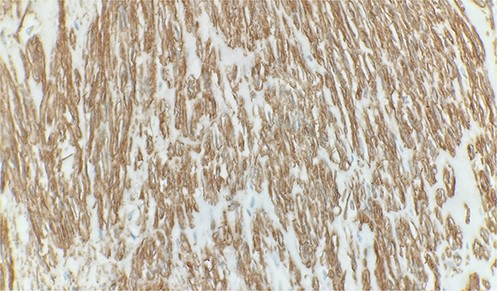

Immunohistochemical stain reveals tumor cells are positive for smooth muscle actin. Immunohistochemistry 40×.

A 70-year-old male patient with a history of prostatic adenocarcinoma presented with testicular swelling. Testicular ultrasound revealed a 4 cm hypoechoic mass at the level of the epididymis. The patient underwent a radical orchiectomy. Pathology demonstrated a 4 cm mass located around the epididymis that was composed of elongated spindle cells arranged in intersecting fascicles. The tumor cells were found to have cigar-shaped nuclei and fibrillary eosinophilic cytoplasm (Fig. 1). Most of the lesions indicated relatively monomorphic cytology. Scattered moderate-to-focally marked nuclear pleomorphism was present. Focal necrosis was present, which may be suggestive of more aggressive biologic behavior. Ki 67% was approximately 10% and the mitotic activity was 7 mitotic figures per 10 high power-fields. The tumor margins were negative, with no invasion of the testicular parenchyma or spermatic cord. Immunohistochemistry showed strong reactivity with desmin and smooth muscle actin (Fig. 2). Overall, findings were diagnostic of low-grade leiomyosarcoma.